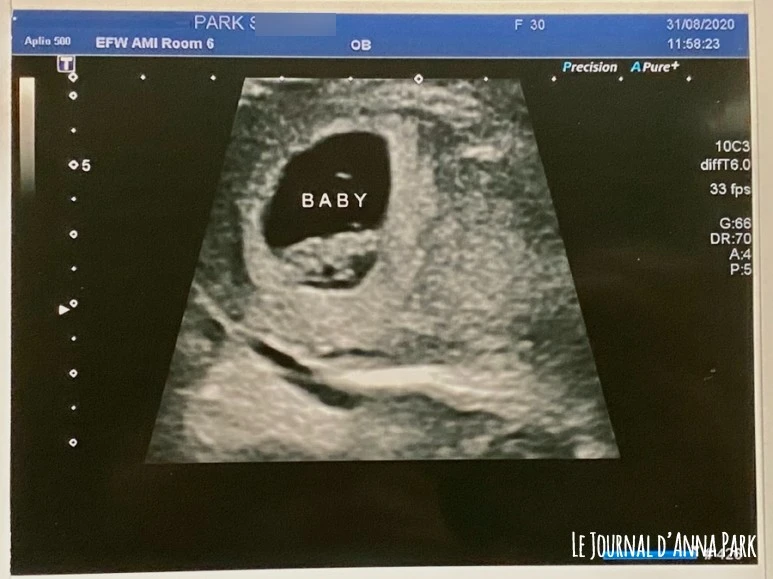

테크니션이 안내해준 초음파실에서 나는 배드 위에 누웠고 남편은 옆에 있는 의자에 앉았다. 테크니션이 내 배 위에 젤을 바르고 초음파기계를 갖다 대고, 우중충한 화면을 보며 아무 말 없이 열심히 길이를 재기 시작했다. 우리도 볼 수 있게 침대 아래쪽에 화면이 하나 더 있었는데, 뭘 하는 건지 알 수가 없었다. 말했는데 못 알아들은 것 같기도 하다. 대충 8주 차 초음파가 어떤 모습인지 인터넷으로 사진을 열심히 찾아봤었기에 눈치껏 보고 있었는데, 도저히 아기같이 보이지 않았다. 그래서 용기를 내어 "Doesn't look like a baby.."라고 했더니 그제야 테크니션이 웃으면서 설명해줬다. “이게 애기야. 왼쪽이 머리야. 가운데 반짝반짝하는 게 심장이야. 심장 박동 좀 볼까? 잘 뛰네! (심장소리는 안 들려주고 박동 그래프만 보인다) 뭐도 정상이고 뭐도 정상이야 (또 못 알아들음)” 암튼 정상이라길래 안심했다. 갑자기 그냥 분리된 것처럼 보이지도 않던 물체가 애기라고 하니 눈물이 났다. 난 안 울 줄 알았는데 정말 울컥할 새도 없이 눈물부터 나더라. 테크니션이 화장실 다녀오라면서 자리를 비워줬다. 동영상 촬영이 금지지만 마치 잠깐 촬영할 수 있게 자리를 비워준 것 같았다. 으앙 눈물 두어 방울 흘린 뒤 일단 화장실부터 다녀왔다.

초음파 검사는 10분 만엔가 금방 끝났다. 센터에서 나가면서 12주 차 초음파, 19주 차 정밀 초음파도 예약하고, 초음파 사진도 받아서 나왔다. 태아 크기가 내 예상보다는 좀 작길래 주수가 다시 적어지겠구나 싶었는데 아니나 다를까 8주 6일 차가 아닌 8주 0일 차였다. 네 쌍의 커플 중에 우리가 제일 먼저 나왔길래 처음에는 '칫.. 우린 10분 만에 끝났는데 다른 애들은 더 길게 초음파 봐주나 보네.. 인종차별인가'하는 자격지심스러운 마음도 들었지만, 결론적으로 다음 초음파를 예약하는 시간이 되게 오래 걸려서 우리가 제일 빨리 끝내고 나올 수 있어 좋았다. 그리고 초음파 보는 게 태아에게는 스트레스를 줄 수 있다는 걸 또 어디서 주워들었기에 그냥 좋게 생각하며 나왔다.

놀라운 건 초음파 사진을 진짜 딱 한 장 밖에 안 준다는 거다. 한국은 막 세 장 네 장씩도 주고 동영상도 녹화해서 어플로 볼 수 있게 해준다던데! 한국의 상황을 알고 있으니 캐나다의 시스템이 그저 더 실망스러울 뿐이다. *친구에게 듣자하니 처음에 접수할 때 사진을 추가로 살 수 있는지 물어보면 몇 장을 usb에 담아 구매할 수 있게 해준다고 한다. 접수 시에 말해야 한다. (나는 이걸 정규 초음파 다 끝나고야 알았네;;;;)

꿀잼이 8주 첫 초음파: 심장이 반짝반짝